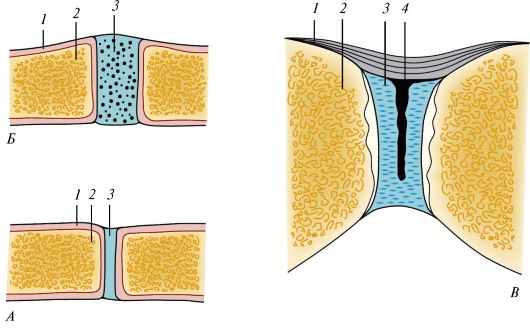

Структура и анатомия синдесмоза: научные иллюстрации